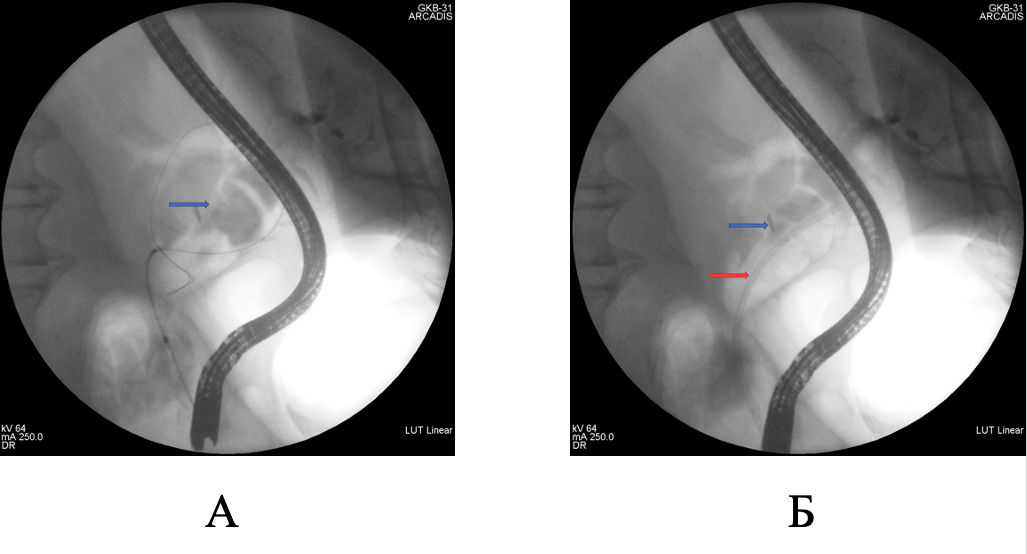

Представлено клиническое наблюдение успешного этапного эндоскопического лечения при гигантском множественном холедохолитиазе. Традиционное хирургическое вмешательство было противопоказано пациентке ввиду выраженных сопутствующих заболеваний и большого анестезиологического риска. Базовым методом мини-инвазивного лечения была контактная литотрипсия, дополненная баллонной дилатацией зоны эндоскопической папиллосфинктеротомии и механической внутрипротоковой литотрипсией. Применение контактной литотрипсии при пероральной транспапиллярной холангиоскопии в сочетании с другими современными способами эндоскопического лечения холедохолитиаза обладает хорошим техническим и клиническим эффектом даже при гигантских размерах билиарных конкрементов.

Будзинский С.А., Шаповальянц С.Г., Воробьева Е.А., Козлова П.С., Соловьев Н.С., Платонова Е.Н., Федоров Е.Д. Успешное эндоскопическое лечение гигантского множественного холедохолитиаза с применением пероральной транспапиллярной холангиоскопии и внутрипротоковой контактной литотрипсии. Анналы хирургической гепатологии. 2023;28(1):109-115. https://doi.org/10.16931/1995-5464.2023-1-109-115

Budzinskiy S.A., Shapovalyants S.G., Vorobyova E.A., Kozlova P.S., Solovjev N.S., Platonova E.N., Fedorov E.D. Successful endoscopic treatment of giant multiple choledocholithiasis using oral transpapillary cholangioscopy and intraductal contact lithotripsy. Annaly khirurgicheskoy gepatologii = Annals of HPB Surgery. 2023;28(1):109-115. (In Russ.) https://doi.org/10.16931/1995-5464.2023-1-109-115